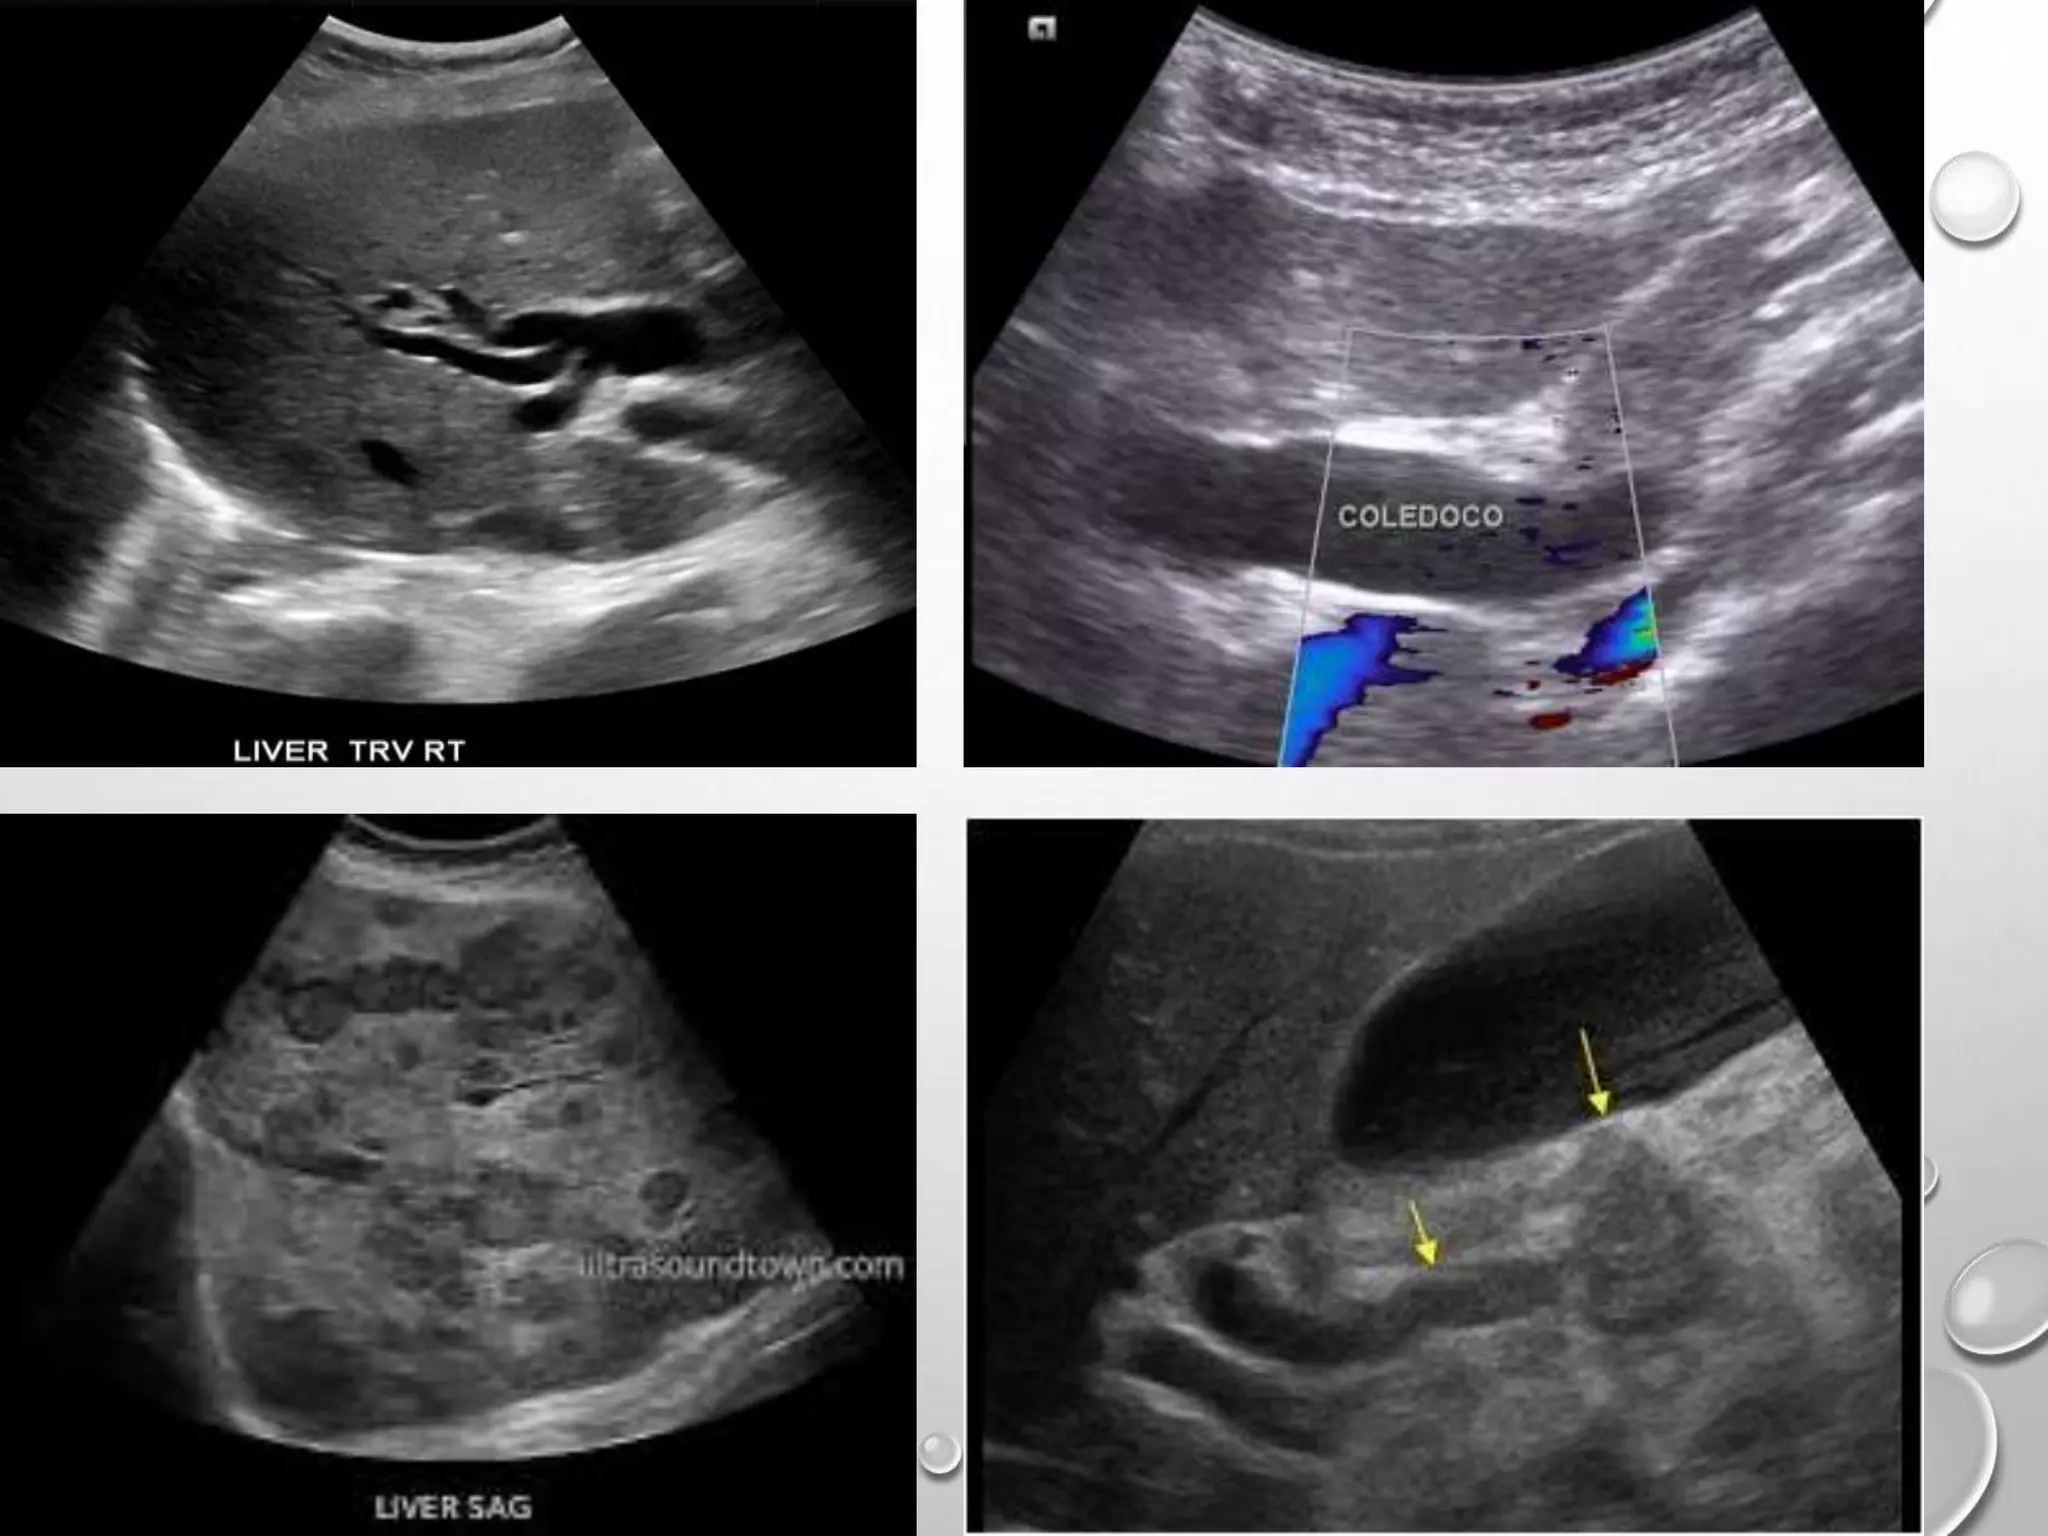

USG ABDOMEN

It is the preliminary investigation of choice

1. Helps in identifying the cause of obstruction

2. Level of obstruction and degree of back pressure changes.

3. Status of the liver and abdominal metastases in suspected malignant obstruction.

4. Splenic enlargement.

5. Presence of ascites.

Limitations of USG-

1) Excess bowel gas, obesity hampers the window.

2) Does not clearly identify distal CBD pathology

3) Except mass lesion in the head of the pancreas, USG usually does not identify the

type of obstruction

USG ABDOMEN It isthe preliminary investigation of choice 1. Helps in identifying the cause of obstruction 2. Level of obstruction and degree of back pressure changes. 3. Status of the liver and abdominal metastases in suspected malignant obstruction. 4. Splenic enlargement. 5. Presence of ascites. Limitations of USG- 1) Excess bowel gas, obesity hampers the window. 2) Does not clearly identify distal CBD pathology 3) Except mass lesion in the head of the pancreas, USG usually does not identify the type of obstruction